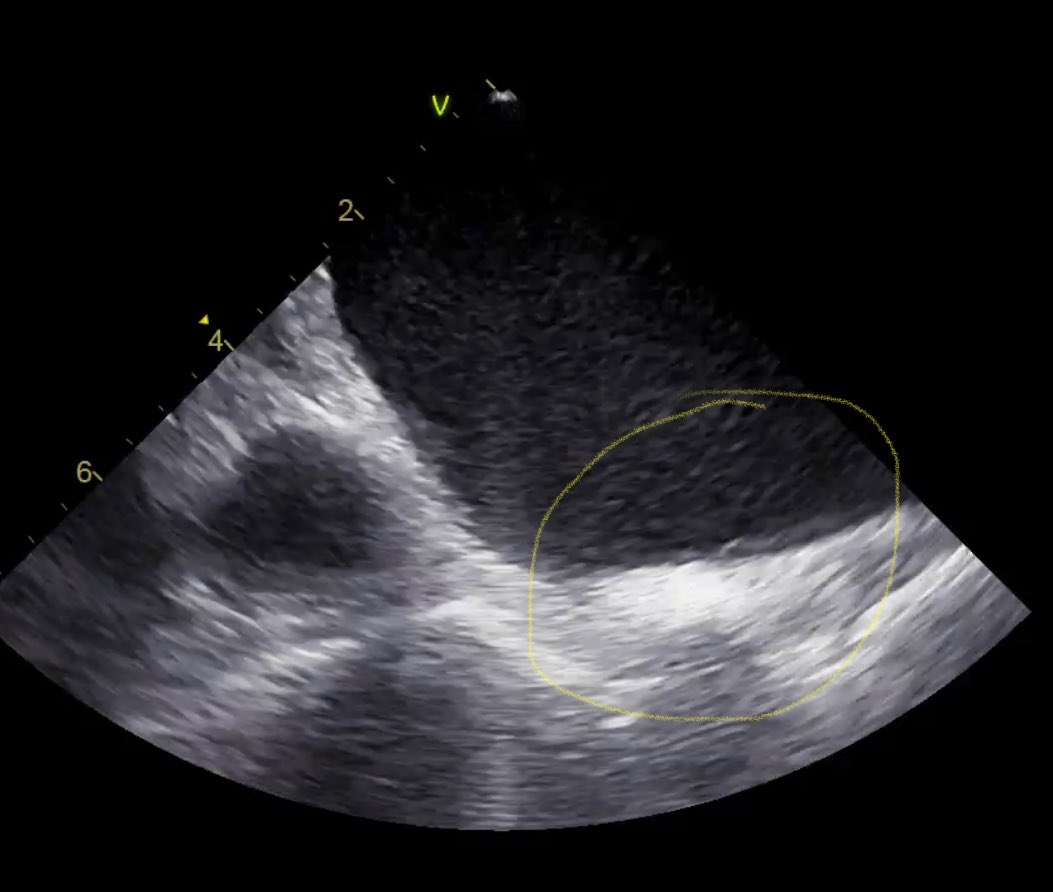

More evidence mounting that lines of block during baseline rhythm are indeed fixed isthmus boundaries for VT. 👏🏻@Davilandre @BidmcCvi

pubmed.ncbi.nlm.nih.gov/38819346/ VT ablation without the need for VT induction and the use of activation map to better understand the substrate.